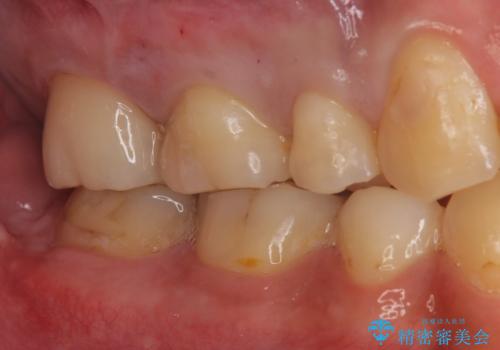

白い被せ物が入り希望に沿った処置となり

大変満足して頂けました。